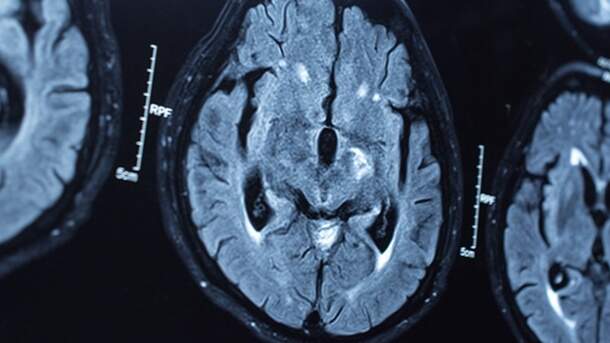

Tipo de lesão cerebral chamada "angiopatia amiloide cerebral", que geralmente sinaliza a doença de Alzheimer, foi encontrada de maneira surpreendente na necrópsia de pessoas mortas pela doença de Creutzfeldt-Jakob. (Foto: Reprodução)

Um tipo de lesão cerebral chamada “angiopatia amiloide cerebral” (depósito de proteínas amiloides nos vasos), que geralmente sinaliza a doença de Alzheimer, foi encontrado de maneira surpreendente na necrópsia de pessoas mortas relativamente jovens (entre 36 e 51 anos) pela DCJ.